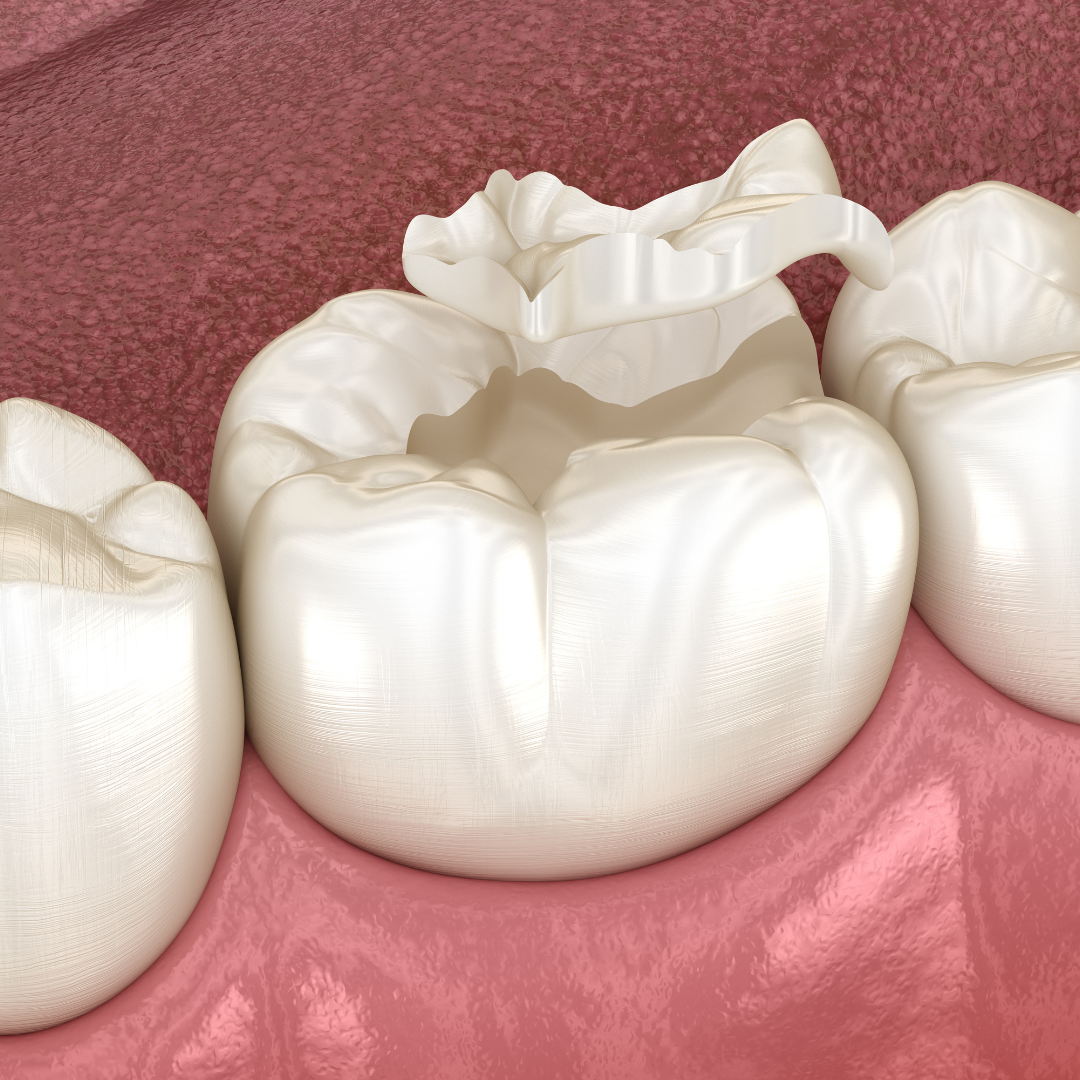

সিল্যান্ট হল এক ধরনের পাতলা প্লাস্টিকের আবরণ, যা সাধারণত মোলার ও প্রি-মোলার দাঁতের উপর প্রয়োগ করা হয়। এই দাঁতগুলোর চর্বিযুক্ত ও গভীর খাঁজ থাকে, যেখানে খাদ্যকণা আটকে যেতে পারে এবং ব্যাকটেরিয়া জন্ম নিতে পারে। সিল্যান্ট এই অংশগুলোকে ঢেকে দেয়, ফলে দাঁতের ক্ষয় হওয়ার ঝুঁকি অনেক কমে যায়।

সিল্যান্ট বসানোর পুরো প্রক্রিয়াটি সহজ, ব্যথাহীন ও দ্রুত সম্পন্ন হয়। এটি সাধারণত ৫-১০ মিনিটের মধ্যে একটি দাঁতে প্রয়োগ করা যায়।

এরপর তরল সিল্যান্ট দাঁতে প্রয়োগ করা হয় এবং এটি দাঁতের ফাটল বা খাঁজের মধ্যে প্রবাহিত হয়।

বিশেষ LED লাইট ব্যবহার করে সিল্যান্ট শক্ত করা হয়, যাতে এটি দীর্ঘস্থায়ী হয়।